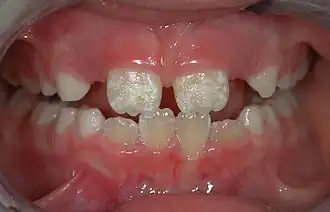

The normal color of enamel varies from light yellow to grayish (bluish) white. It has been suggested that the color is determined by differences in the translucency of enamel, yellowish teeth having a thin, translucent enamel through which the yellow color of the dentin is visible and grayish teeth having a more opaque enamel. The translucency may be attributable to variations in the degree of calcification and homogeneity of the enamel. At the edges of teeth where there is no dentin underlying the enamel, the color sometimes has a slightly blue or translucent off-white tone, easily observable on the upper incisors. Since enamel is semitranslucent, the color of dentin and any material underneath the enamel strongly affects the appearance of a tooth. The enamel on primary teeth has a more opaque crystalline form and thus appears whiter than on permanent teeth.

There are 14 different types of amelogenesis imperfecta.[3] The hypocalcification type, which is the most common, is an autosomal dominant condition that results in enamel that is not completely mineralized.[53] Consequently, enamel easily flakes off the teeth, which appear yellow because of the revealed dentin. The hypoplastic type is X-linked and results in normal enamel that appears in too little quantity, having the same effect as the most common type.[53]